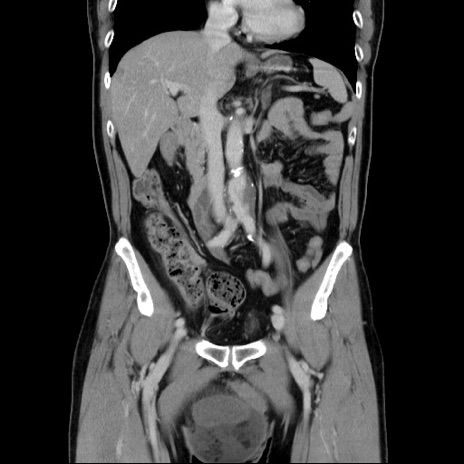

症例34(冠状断像)

【症例】60歳代 男性

【主訴】右鼠径部膨隆

【現病歴】1年程前より右鼠径部膨隆あり。自己にて還納可能だったため放置していた。3時間前より右鼠径部の脱出を認め、還納困難となり受診。

【既往歴】高血圧

【身体所見】右鼠径部に小児頭大の膨隆あり。弾性硬であり、用手還納は困難。左鼠径部にも膨隆を認める。脱出はなし。